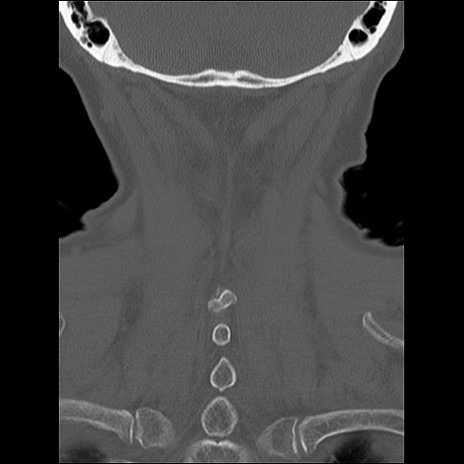

症例48 頚椎CT(冠状断像)

頚椎CT